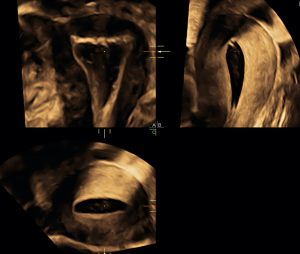

ÉCHOGRAPHIE OBSTÉTRICALE